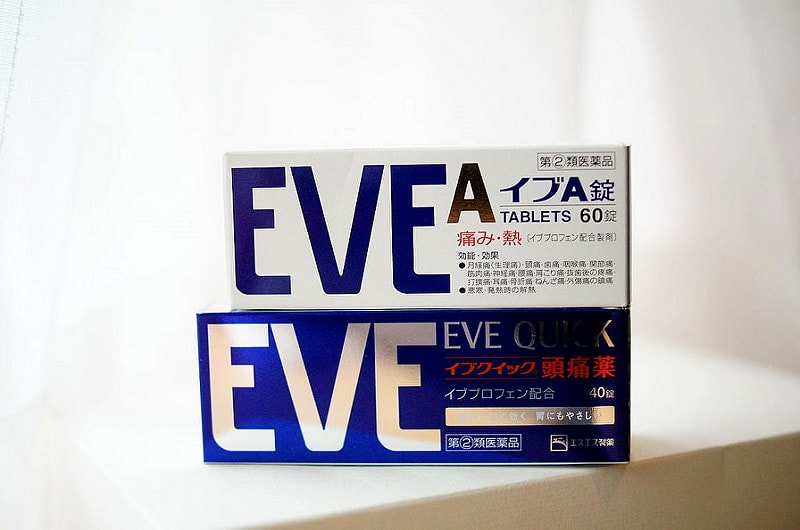

馬兒跟D哥大力推薦的EVE,據說D哥還買一打放家裡

據說也是日本人的家庭常備藥啦

原來女孩子那個來都會吃止痛藥嗎?

我都會忍欸~~就覺得忍過就是自己的(?)

不過身邊朋友都大力推薦EVE我只好買買看了XDDD

據說是對痛症都OK啦~